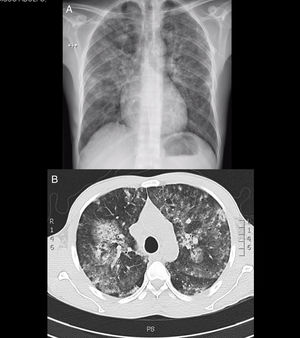

He had severe anaemia, renal dysfunction and mixed opacities in both pulmonary fields (Fig. 1 and Table 1). He was diagnosed pulmonary-renal syndrome and treatment commenced with high doses of steroids and blood cell transfusion. At first the diagnosis of systemic lupus erythmatosus (SLE) was considered due to the finding of hypocomplementemia. Additional studies found multiple antibody positivity: ANCA (antimyeloperoxidase and antiproteinase-3), ANA, anti-Ro, anti-La, lupus anticoagulant, rheumatoid factor and anticardiolipin IgM. Anti-Sm, anti-DNA and anti-basement glomerular membrane antibodies were negative.